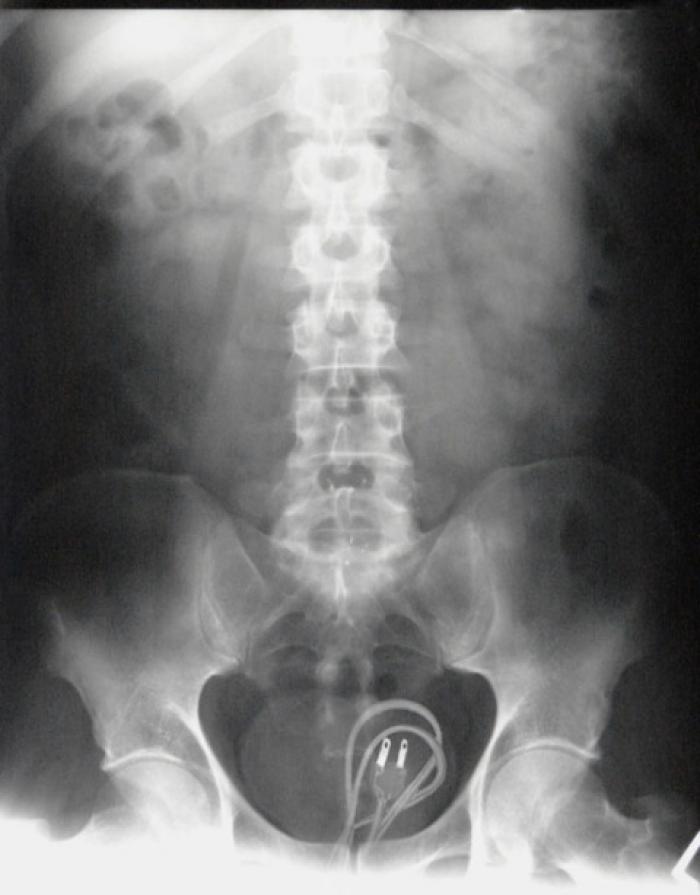

Polițiștii au parte de cele mai amuzante întâmplări, iar infractorii tind să aibă cele mai inventive modalități de a ascunde obiecte, alegând de multe ori posteriorul